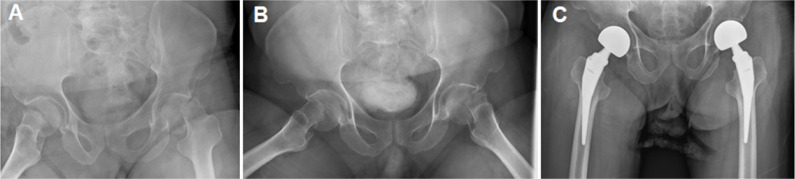

Purpose: There is limited evidence regarding the outcomes of hip hemiarthroplasty (HA) following trauma in individuals living with Down syndrome (DS). This study aims to summarize the outcomes of hip HA in a series of individuals living with DS following femoral neck fractures.

Materials and methods: This retrospective study includes five cases of hip HA in four individuals with DS and displaced femoral neck fractures. Subjects (four males) had a mean age of 49.3 years (range, 26.1-59.7 years) at the time of surgery. All subjects presented with hip pain, loss of weight-bearing ability, and decreased activity level as reported by the subject caregivers. In all cases, the precise time of injury was not known.

Results: After a mean follow-up of 15.2 months, all subjects had returned to the pre-injury activity level without any recorded complications. One individual died 32 months after surgery for unrelated causes; the remaining subjects are alive and ambulating without pain at a mean of 24.2 months since the surgery.

Conclusion: When treating femoral neck fractures in those living with DS, careful history taking should be performed as regards the timing of trauma and the individual's functional status. Hip HA seems a viable treatment option for those living with DS if a proper surgical procedure is utilized.